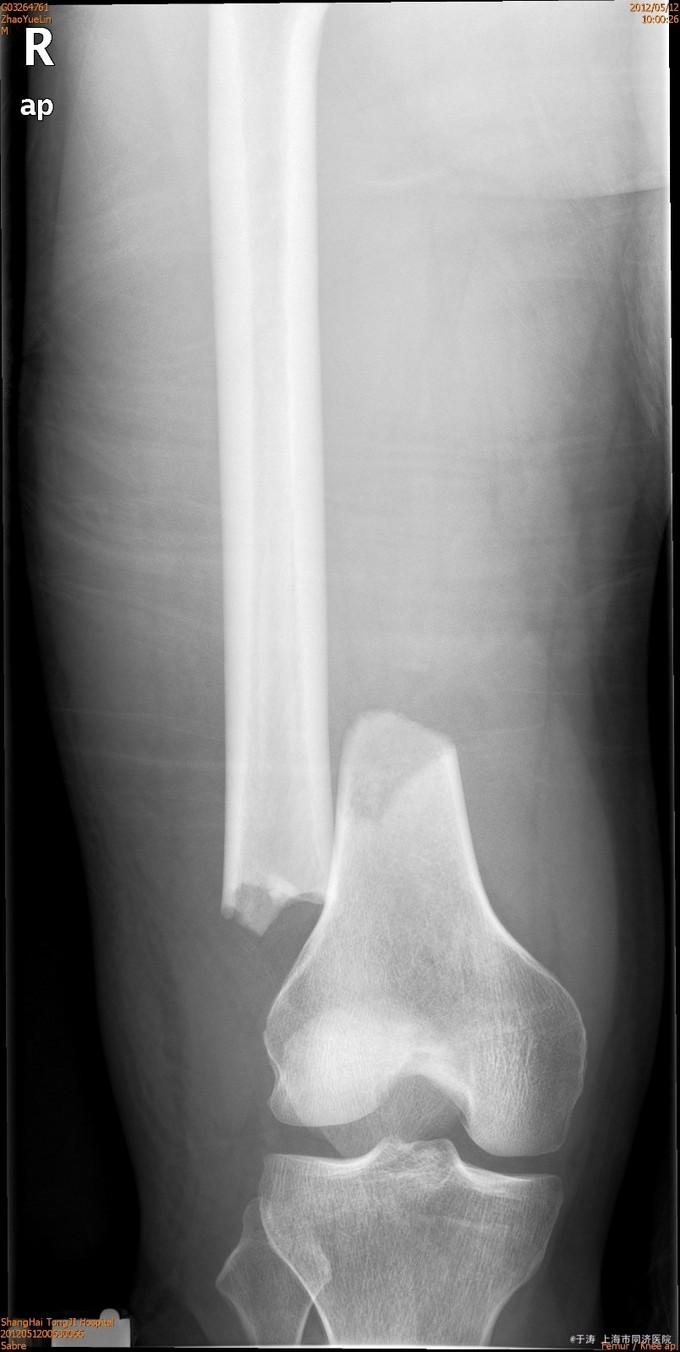

患者男,55岁,因高处坠落后右大腿疼痛伴活动障碍5小时入院。患者入院前5小时不慎从高处坠落,当即出现右大腿下端疼痛,尿道出血,胸痛,无大汗淋漓、头痛、头晕、腹痛、腹胀等。急诊X线示右股骨髁上骨折,CT示头皮血肿,右下肺挫裂伤,气胸。

查体:神清,右大腿下端肿胀、瘀斑,局部压痛,可及骨擦感、骨擦音,右小腿及腘窝可见皮肤擦伤,患肢远端感觉血运可。

诊断为右股骨远端骨折,生命体征平稳后,行切开复位内固定术。